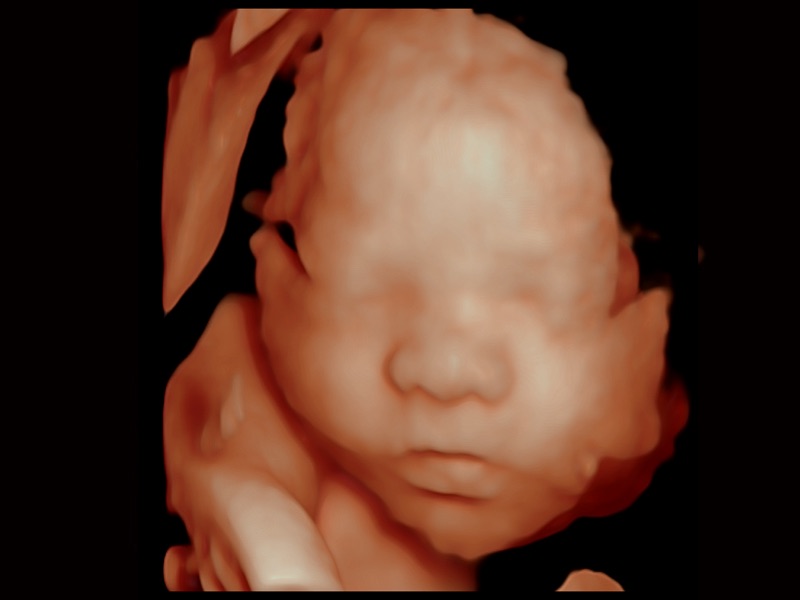

• 妇产科应用

• 光影成像

三维光影成像技术采用新型的渲染方式,增强边缘信息,使得轮显示清晰完整,为临床提供丰富、直观的三维结构,提供临床诊断准确性。